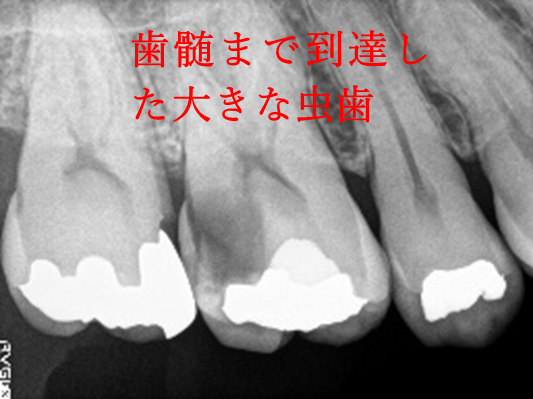

治療内容

歯髄(神経および血管)まで到達する大きな虫歯でしたので、抜髄(歯髄を取り除く)をし、ファイバーコアをいれ、オールセラミック冠を被せました。